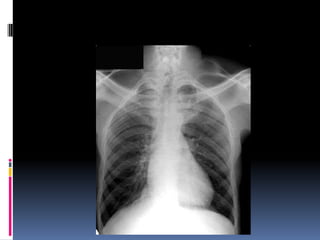

Underpenetrated Film

Hemi diaphragms are obscured

Pulmonary markings more prominent than they actually

Over penetrated Film

 Lung fields darker than

normal—may obscure subtle

pathologies

•   See spine well beyond the

diaphragms

•   Inadequate lung detail